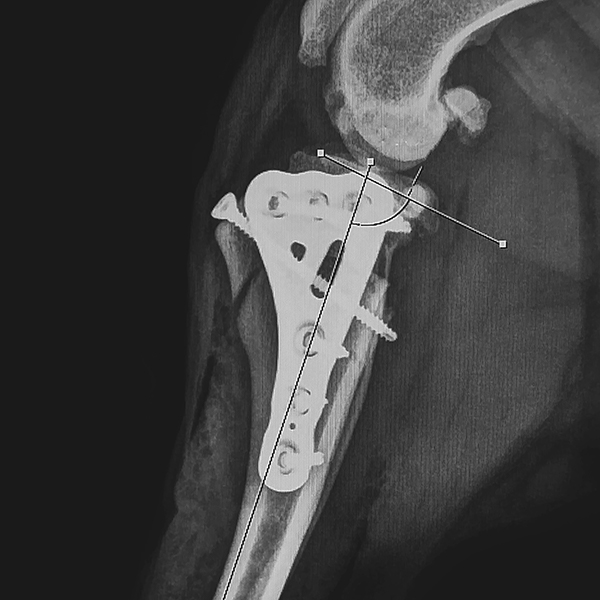

Our CBLO Workshops are designed exclusively for veterinarians seeking to expand their expertise in the Center of Rotation of Angulation-Based Levelling Osteotomy (CBLO) procedure, a surgical technique used to treat cranial cruciate ligament (CCL) rupture in dogs. Our comprehensive program covers stifle anatomy, precise diagnosis of CCL rupture, the correct approach to the stifle joint, thorough stifle examinations, meniscus treatment, the CBLO technique, strategic pre-operative planning, and solutions for potential pitfalls. Combining lectures, demonstrations, and hands-on training with saw bone models and/or cadaveric models, this workshop ensures you acquire practical proficiency under the guidance of experienced surgeons. By the end of the workshop, you will possess a deep understanding of stifle anatomy, the biomechanics of CCL rupture, accurate diagnostic skills, meniscus tear treatment, and the ability to perform CBLO safely and effectively, plan for successful CBLO surgeries, and avoid common pitfalls and complications. Whether you are new to CBLO or seeking to refine your skills, this workshop is ideal for veterinarians dedicated to enhancing their expertise in this area.